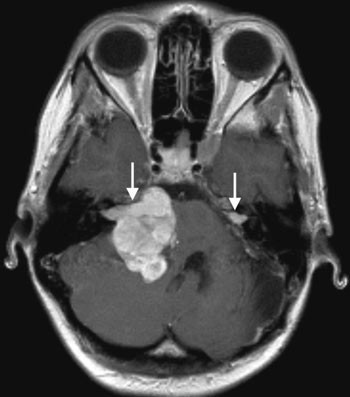

Det kliniske bildet ved nevrofibromatose type 2 domineres av symptomer og tegn som skyldes utvikling av multiple svulster. Om lag 95 % av personer med sykdommen vil utvikle bilateralt vestibularisschwannom (1), som vist i figur 1. Hvorfor vestibularisdelen av 8. hjernenerve er predileksjonssted, er ikke kjent. Schwannomer på andre hjernenerver og på perifere nerver, intrakraniale og intraspinale meningeomer, ependymomer og lavgradige gliomer er andre svulster assosiert med sykdommen (4). Spinale svulster, som vist i figur 2, kan påvises hos 80 – 90 % av personer med nevrofibromatose type 2 (4). Imidlertid vil kun om lag 30 % av disse ha behov for spinal kirurgi (9).